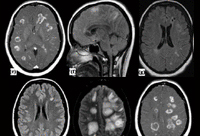

doenças neurológicas

Grupo de pesquisa da UNIRIO utiliza inteligência artificial para estudo de doenças neurológicas

(Notícia: Gabriella Praça/Jornalista Comso)